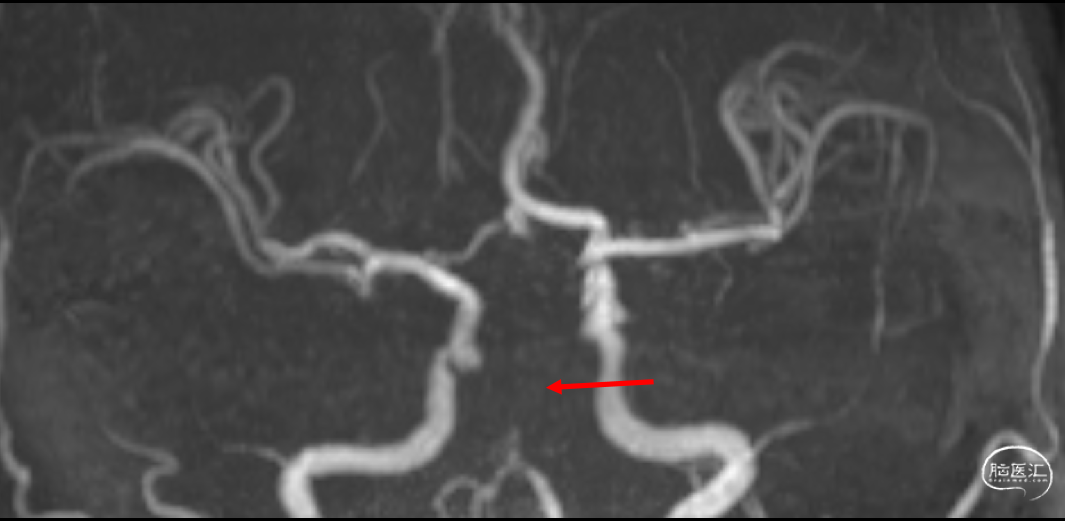

术前影像学检查

头颅MRI+MRA(入院27分钟):右侧丘脑、脑干及双侧小脑半球急性梗死可能;左侧基底节区软化灶;双侧大脑后动脉及基底动脉纤细,局部显示欠清。

定位:基底动脉

初步诊断:1、急性脑梗死(TOAST:大动脉粥样硬化型),2、高血压病,3、基底动脉狭窄